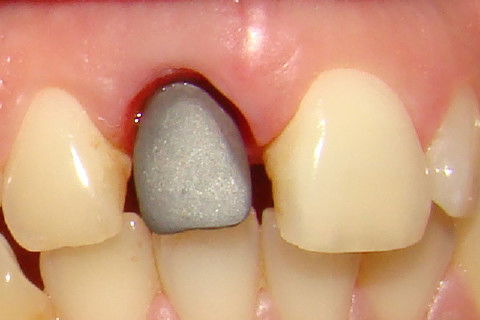

Vista vestibular da coroa temporária, que dará o format ideal dos tecidos gengivais

Paciente com implante feito em curso de atualização, chega ao consultório para reabertura e coroa metalo-ceramica unitária, com grande depressão gengival na vestibular do elemento 11. Feita a reabertura com concomitante enxerto de tecido conjuntivo para otimizar os tecidos moles, aguardamos 3 semanas para inicio das moldagens para a coroa temporária. Após colocação e ajustes da coroa temporária parafusada, aguardamos 3 meses para completa maturação dos tecidos e então fizemos nova moldagem, com personalização do transferente para moldeira aberta individual e fizemos coros metalo-cerâmica parafusada.